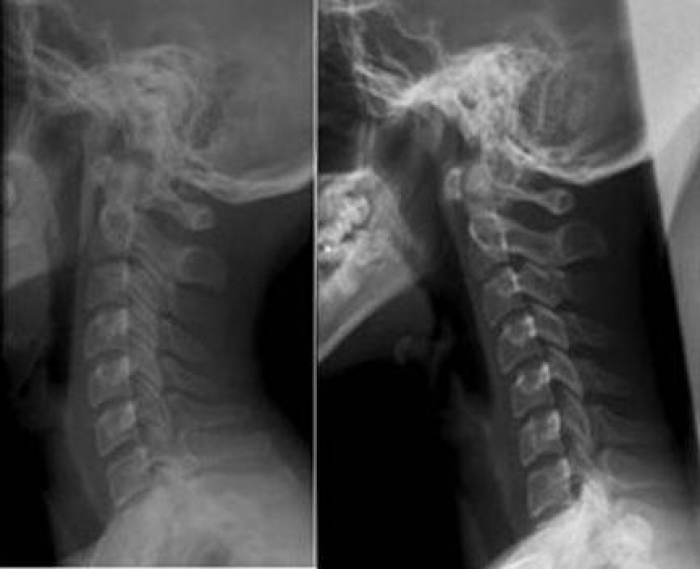

Для подтверждения диагноза проводят рентгенографию. Этот метод позволяет определить степень искривления или выпрямления шейного отдела позвоночника.

Рентгенографию выполняют в двух проекциях. Также могут быть назначены компьютерная томография (КТ) или магнитно-резонансная томография (МРТ). На основе полученных данных оценивается состояние мягких и твердых тканей. Защемление нервов или кровеносных сосудов, а также другие патологические изменения можно выявить на ранних стадиях.